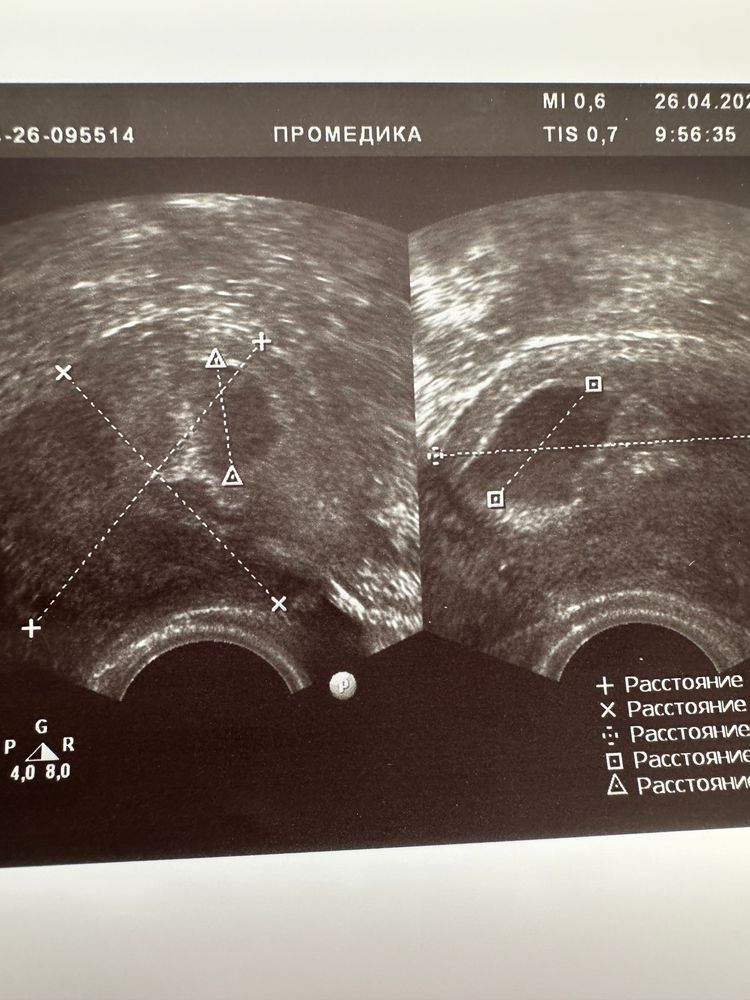

Девочки,у меня всё сложно,у кого так было?Хгч сначала рос 26.8-67.2-138.3-159.3.Последний прирост плохой конечно,но сегодня сдала ещё раз.Пришла на УЗИ,боялась что внематочная.Врач сказала плодное яйцо есть в матке,но так как я сказала что хгч не удвоился поставила под вопрос замершую и сказала придти через неделю,если будет эмбрион и сердцебиение всё ок.По месячным срок 5 недель и 5 дней.Но я ещё думаю за этот хгч,в гемотесте странные какие то референсы,и если отталкиваться от других лабораторий,например Инвитро,ХГЧ у меня должен быть точно 1000,так как по месячных 5,5,ну даже 3 недели по любому есть.Понимаю,что вряд ли исход хороший,но может кто то сталкивался с таким?😞

Алена, в общем по УЗИ всё соответствует,но вот хгч этот вводит в заблуждение 🤔Но я записалась через неделю на узи,может всё нормально будет всё таки

Все бы ничего…если б не ПЯ направильной формы(((

По узи у вас пя соответствует сроку. Смущает плохой рост ХГЧ. Попробуйте пересдать в другой лаборатории.

Когда вы пошли на узи хгч сколько был?

Рост плохой, форма пя тоже смущает, к сожалению